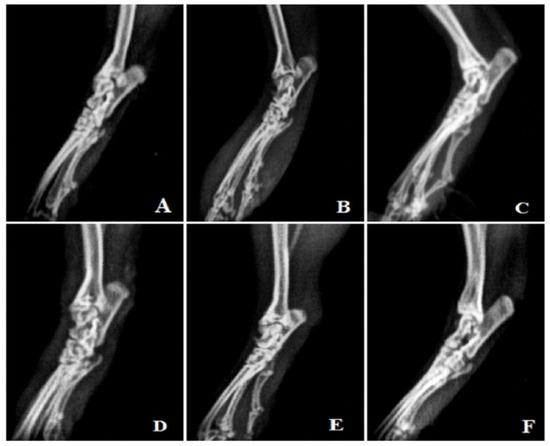

3.4.10. Radiological Analysis